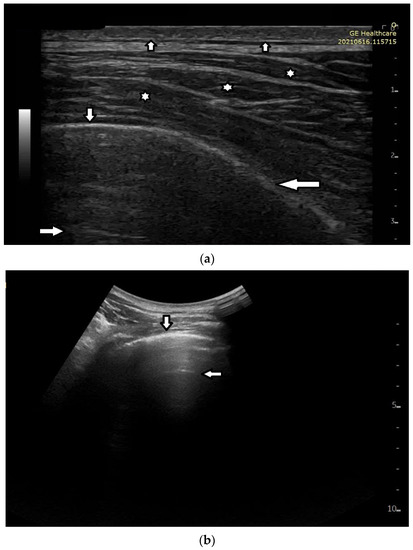

While monitoring the interstitial and alveolar involvement, we observe more and more confluent B lines which can evolve in a so-called white lung artifact which, in turn, can subsequently change to consolidation (see Figure 1) [5,6]. What does the image of B lines and consolidations depend on?

Isolated B lines are related to isolated acoustic traps and this probably occurs in the first stages of a pathology. When the number of the acoustic traps increases, due to the progression of a pathology, numerous B lines are observed. When their number further increases, they are close to each other and can be even mutually linked. In this case, confluent artifacts logically appear. When the ratio between aerated spaces and interstitial volumes drastically decreases within a lung region, then a lung configuration where small separated aerated spaces are immersed in an interstitial volume is expected. This is probably the lung configuration which is at the basis of the White Lung artifact. Obviously, when the last small aerated spaces also disappear, a clear consolidation naturally emerges.

Figure 1. Gradual loss of lung aeration in ultrasound. (a) normally aerated lung, (b) single vertical artifacts, (c) multiple vertical artifacts, and (d) subpleural consolidation.